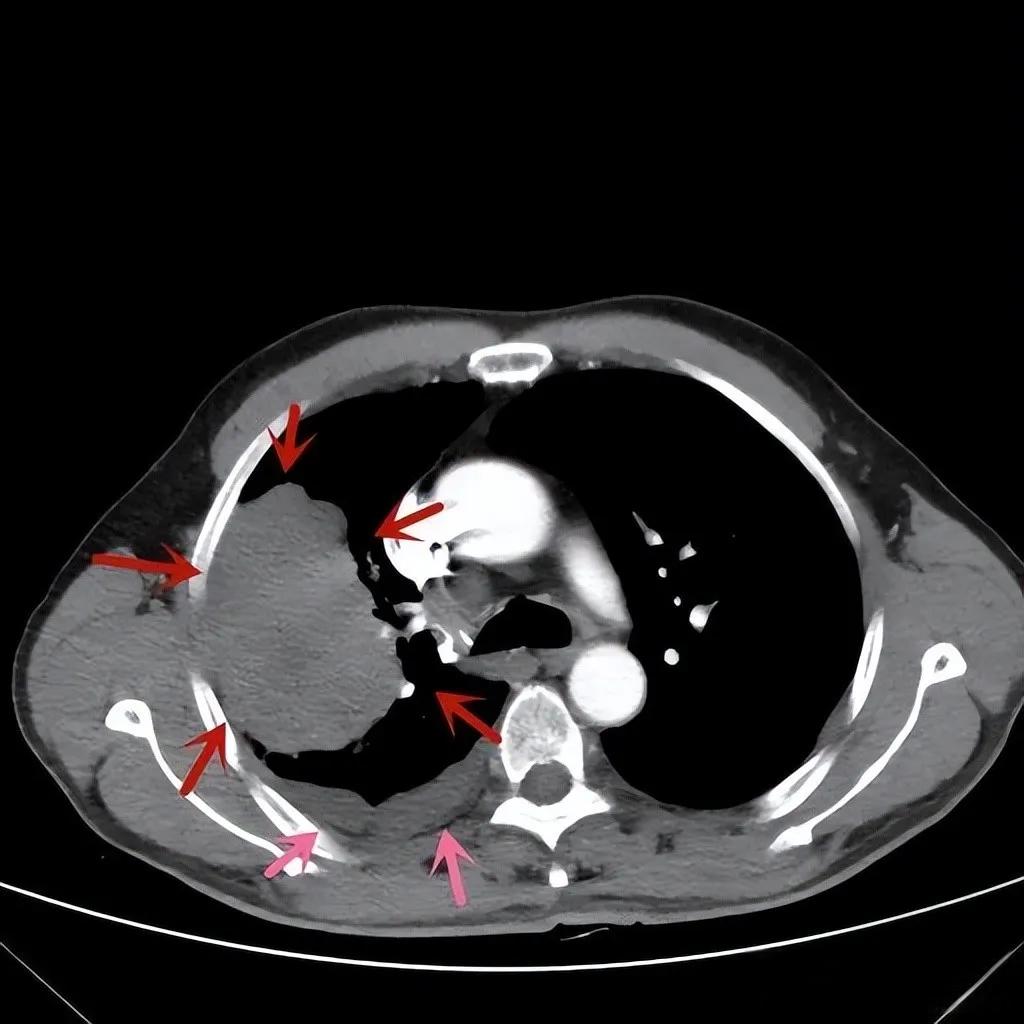

卡瑞利珠单抗,这种由中国恒瑞医药自主研发的PD-1抑制剂,正在肺癌治疗领域掀起一场革命。近期公布的研究数据显示,卡瑞利珠单抗联合化疗不仅能够显著延长肺癌患者的生存期,甚至能让一些巨大肺癌肿瘤退缩90%,让患者重新回归正常生活。

更令人惊叹的是,卡瑞利珠单抗联合化疗能够使一些巨大肺癌肿瘤退缩90%。一位接受治疗的患者在接受采访时说:“我原本以为自己活不过一年,但现在我已经正常生活了三年多,肿瘤几乎消失了。”这种治疗效果在传统化疗中是难以想象的。